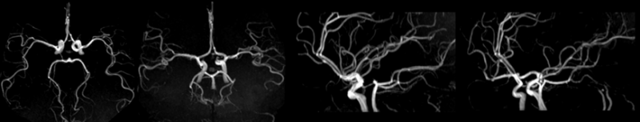

MРA означает магнитно-резонансная ангиография. Мра сосудов головного мозга проводится для оценки нарушений в системе притока артериальной крови к головному мозгу.

Трехмерная (3D) времяпролетная ангиография time-of-flight (TOF) МRА является наиболее распространенным методом, используемым для оценки системы артериального кровоснабжения головного мозга.

МРА 3D TOF обеспечивает более высокий сигнал-шум (signal-to-noise) и короткое время обработки изображений. MРA головного мозга проста в выполнении и не требует контрастного усиления.

Магнитно-резонансная ангиография (МРА) широко применяется в исследованиях магистральных артерий в экстра- и интракраниальном отделах. МРА достаточно информативна для визуализации сонных, позвоночных и внутримозговых артерий.

На МР-ангиограммах сосуды визуализируются как трубчатые структуры с повышенной интенсивностью сигнала на фоне низкоинтенсивных прилегающих тканей. Сигнал от кровотока в них однородный, определяется четкостью контуров артерий, вен и венозных пазух.

MP-ангиография, проведенная на уровне артериального круга мозга, позволяет визуализировать внутренние сонные и средние мозговые артерии, проксимальные отделы передних мозговых артерий, основную и задние мозговые артерии. Передние и задние соединительные артерии, а также дистальные отделы мозговых артерий не определяются из-за малого их диаметра.

МРА позволяет обнаружить патологические изменения магистральных сосудов головного мозга: извитость с петлеобразованием и обеднение периферического сосудистого рисунка передней, средней и задней мозговых артерий (ПМА, СМА, ЗМА) с обеих сторон. При тромбозе на МРА определяется «обрыв» сосуда и не визуализируются ветви сосудов, расположенные дистальнее окклюзии.

При стенозе артерии выявляют равномерное или неравномерное сужение сосуда в определенном сегменте, в то же время при гипоплазии артерии в основном обнаруживают равномерное сужение сосуда на всем протяжении.